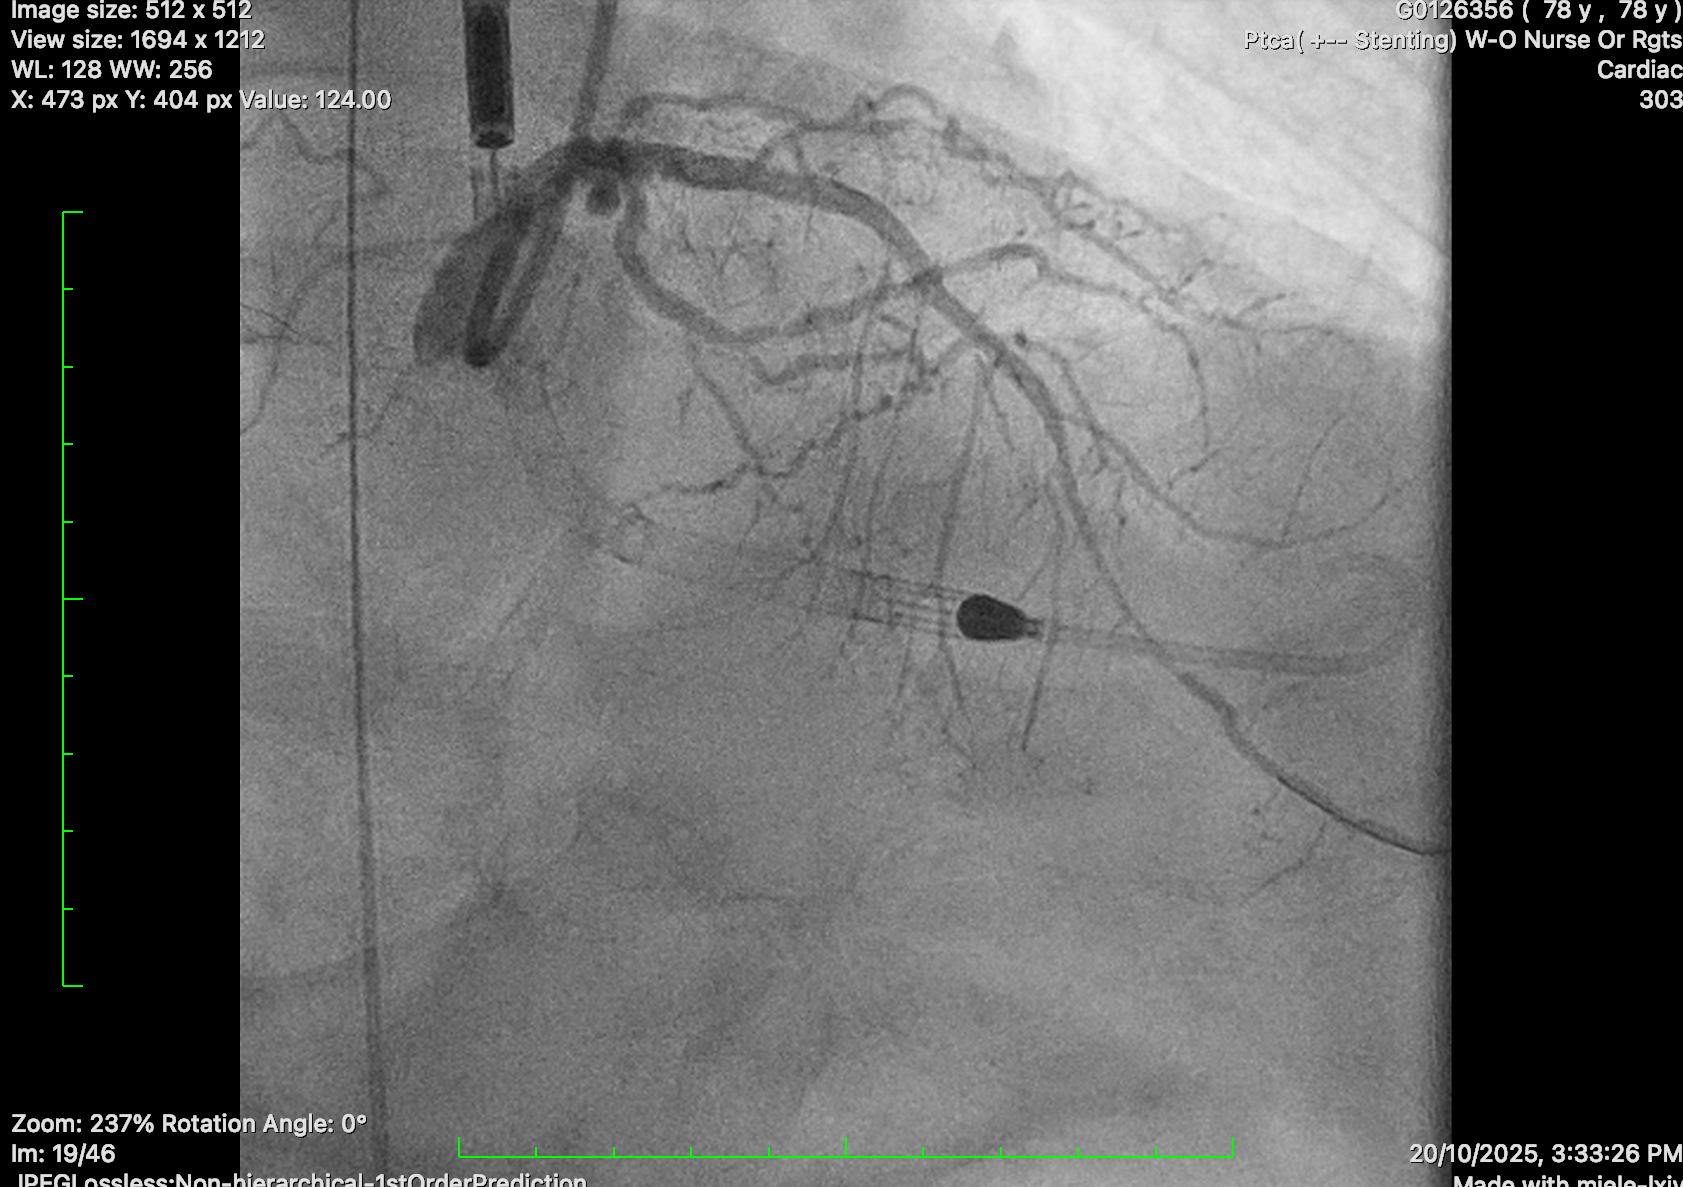

PCI to LCA: EBU 3.0 7 Fr guide catheter. Successful wiring to distal LAD with workhorse wire. Unable to cross SC 1.0 balloon. Exchanged for Rotawire Extra Floppy. 1.25mm burr for rotational atherectomy with significant decelerations. Still failed to deliver SC 1.0 and 1.5 balloon. Upsized to 1.5mm Rotaburr. Further dilated with SC 1.5 and 2.0 balloon, then shockwave with 2.5 balloon and further predilatation with NC balloon. DES 2.25/30, 3.0/18 and 3.5/24 deployed. Post dilatation with NC 4.0 and 3.5 balloon.

Satisfactory results

PCI to RCA: JR 4.0 guide catheter. Critical RCA lesion crossed with Fielder XT-R supported by microcatheter. Predilated with semi-compliant balloon and 3.0/40, 3.5/22 and 3.5/9 stents deployed. Post dilated with NC 3.25 balloons.